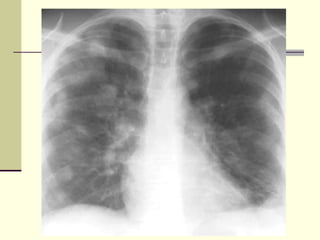

NORMAL CHEST X-RAY L- Lung T- Trachea AK- Aortic Knob A- Ascending Aorta H- Heart R- Ribs P- Pulmonary Artery S- Spleen

NORMAL CHEST X-RAYL- Lung T- Trachea AK- Aortic Knob A- Ascending Aorta H- Heart R- Ribs P- Pulmonary Artery S- Spleen